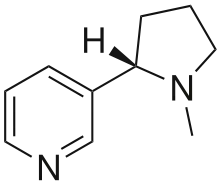

Nicotine

Nicotine, which is contained in cigarettes and other smoked tobacco products, is a stimulant and is one of the main factors leading to continued tobacco smoking. Nicotine is a highly addictive psychoactive chemical. When tobacco is smoked, most of the nicotine is pyrolyzed; a dose sufficient to cause mild somatic dependency and mild to strong psychological dependency remains. The amount of nicotine absorbed by the body from smoking depends on many factors, including the type of tobacco, whether the smoke is inhaled, and whether a filter is used. There is also a formation of harmane (a MAO inhibitor) from the acetaldehyde in cigarette smoke, which seems to play an important role in nicotine addiction[243] probably by facilitating dopamine release in the nucleus accumbens in response to nicotine stimuli. According to studies by Henningfield and Benowitz, nicotine is more addictive than cannabis, caffeine, alcohol, cocaine, and heroin when considering both somatic and psychological dependence. However, due to the stronger withdrawal effects of alcohol, cocaine and heroin, nicotine may have a lower potential for somatic dependence than these substances.[244][245] About half of Canadians who currently smoke have tried to quit.[246] McGill University health professor Jennifer O'Loughlin stated that nicotine addiction can occur as soon as five months after the start of smoking.[247]

Although nicotine does play a role in acute episodes of some diseases (including stroke, impotence, and heart disease) by its stimulation of adrenaline release, which raises blood pressure,[103] heart and respiration rate, and free fatty acids, the most serious longer term effects are more the result of the products of the smoldering combustion process. This has led to the development of various nicotine delivery systems, such as the nicotine patch or nicotine gum, that can satisfy the addictive craving by delivering nicotine without the harmful combustion by-products. This can help the heavily dependent smoker to quit gradually while discontinuing further damage to health.

The carcinogenity of tobacco smoke is not explained by nicotine per se, which is not carcinogenic or mutagenic, although it is a metabolic precursor for several compounds which are. In addition, it inhibits apoptosis, therefore accelerating existing cancers.[252] Also, NNK, a nicotine derivative converted from nicotine, can be carcinogenic.

Nicotine, although frequently implicated in producing tobacco addiction, is not significantly addictive when administered alone.[253] The addictive potential manifests itself after co-administration of an MAOI, which specifically causes sensitization of the locomotor response in rats, a measure of addictive potential.[254]